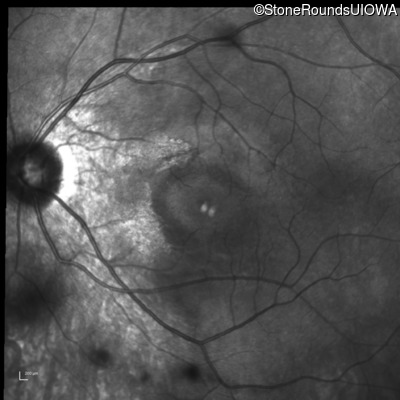

Infrared Fundus Photograph - Right - 20/20

Exemplar